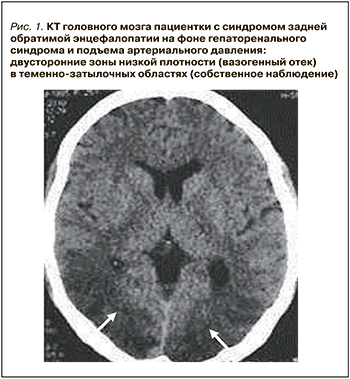

Компьютерная томография (КТ) или магнитно-резонансная томография (МРТ) являются необходимыми методами диагностики СЗОЭ, позволяющими выявить его морфологическую основу – вазогенный отек головного мозга. При классическом варианте СЗОЭ (до 70% всех наблюдений) вазогенный отек мозга локализуется в теменно-затылочных отделах больших полушарий. На КТ он представлен зонами низкой плотности (рис. 1). Методом выбора для окончательной диагностики СЗОЭ служит МРТ. Вазогенный отек головного мозга хорошо визуализируется в режиме МРТ FLAIR (инверсия–восстановление с подавлением сигнала от воды) в виде гиперинтенсивного сигнала (рис. 2) [8, 9].